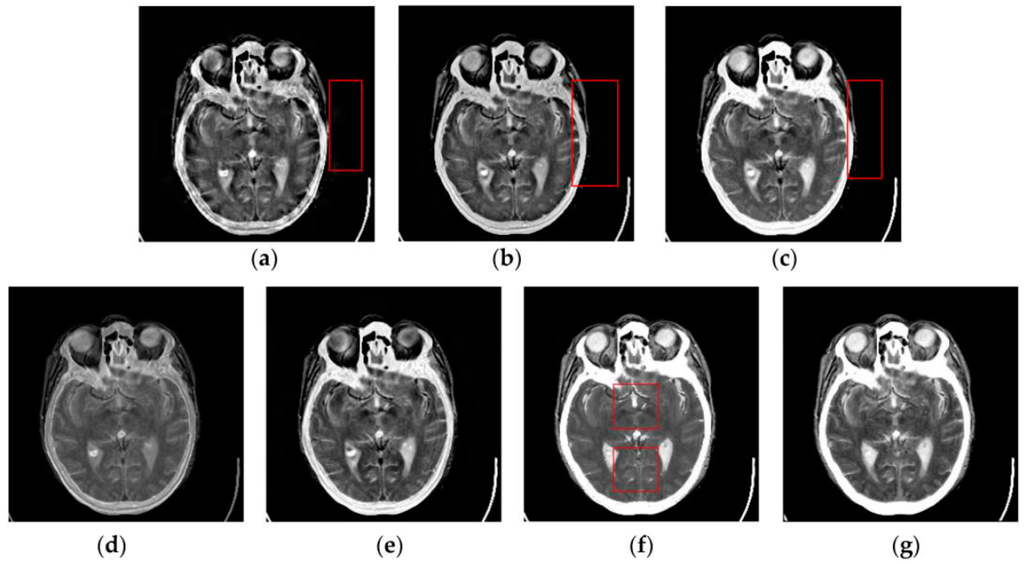

4.2. Visual Comparisons of Fused Results